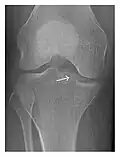

- a

- b

- c

Figure 3: A 26-year-old man presenting with wrist pain after being assaulted. (a) Initial anteroposterior radiograph shows a subtle linear lucency within the scaphoid extending to the scaphocapitate articular surface that was overlooked (arrow). (b) Initial "scaphoid" view was negative. (c) Followup anteroposterior radiographs, 12 days later, shows obvious scaphoid fracture (arrows).[1]